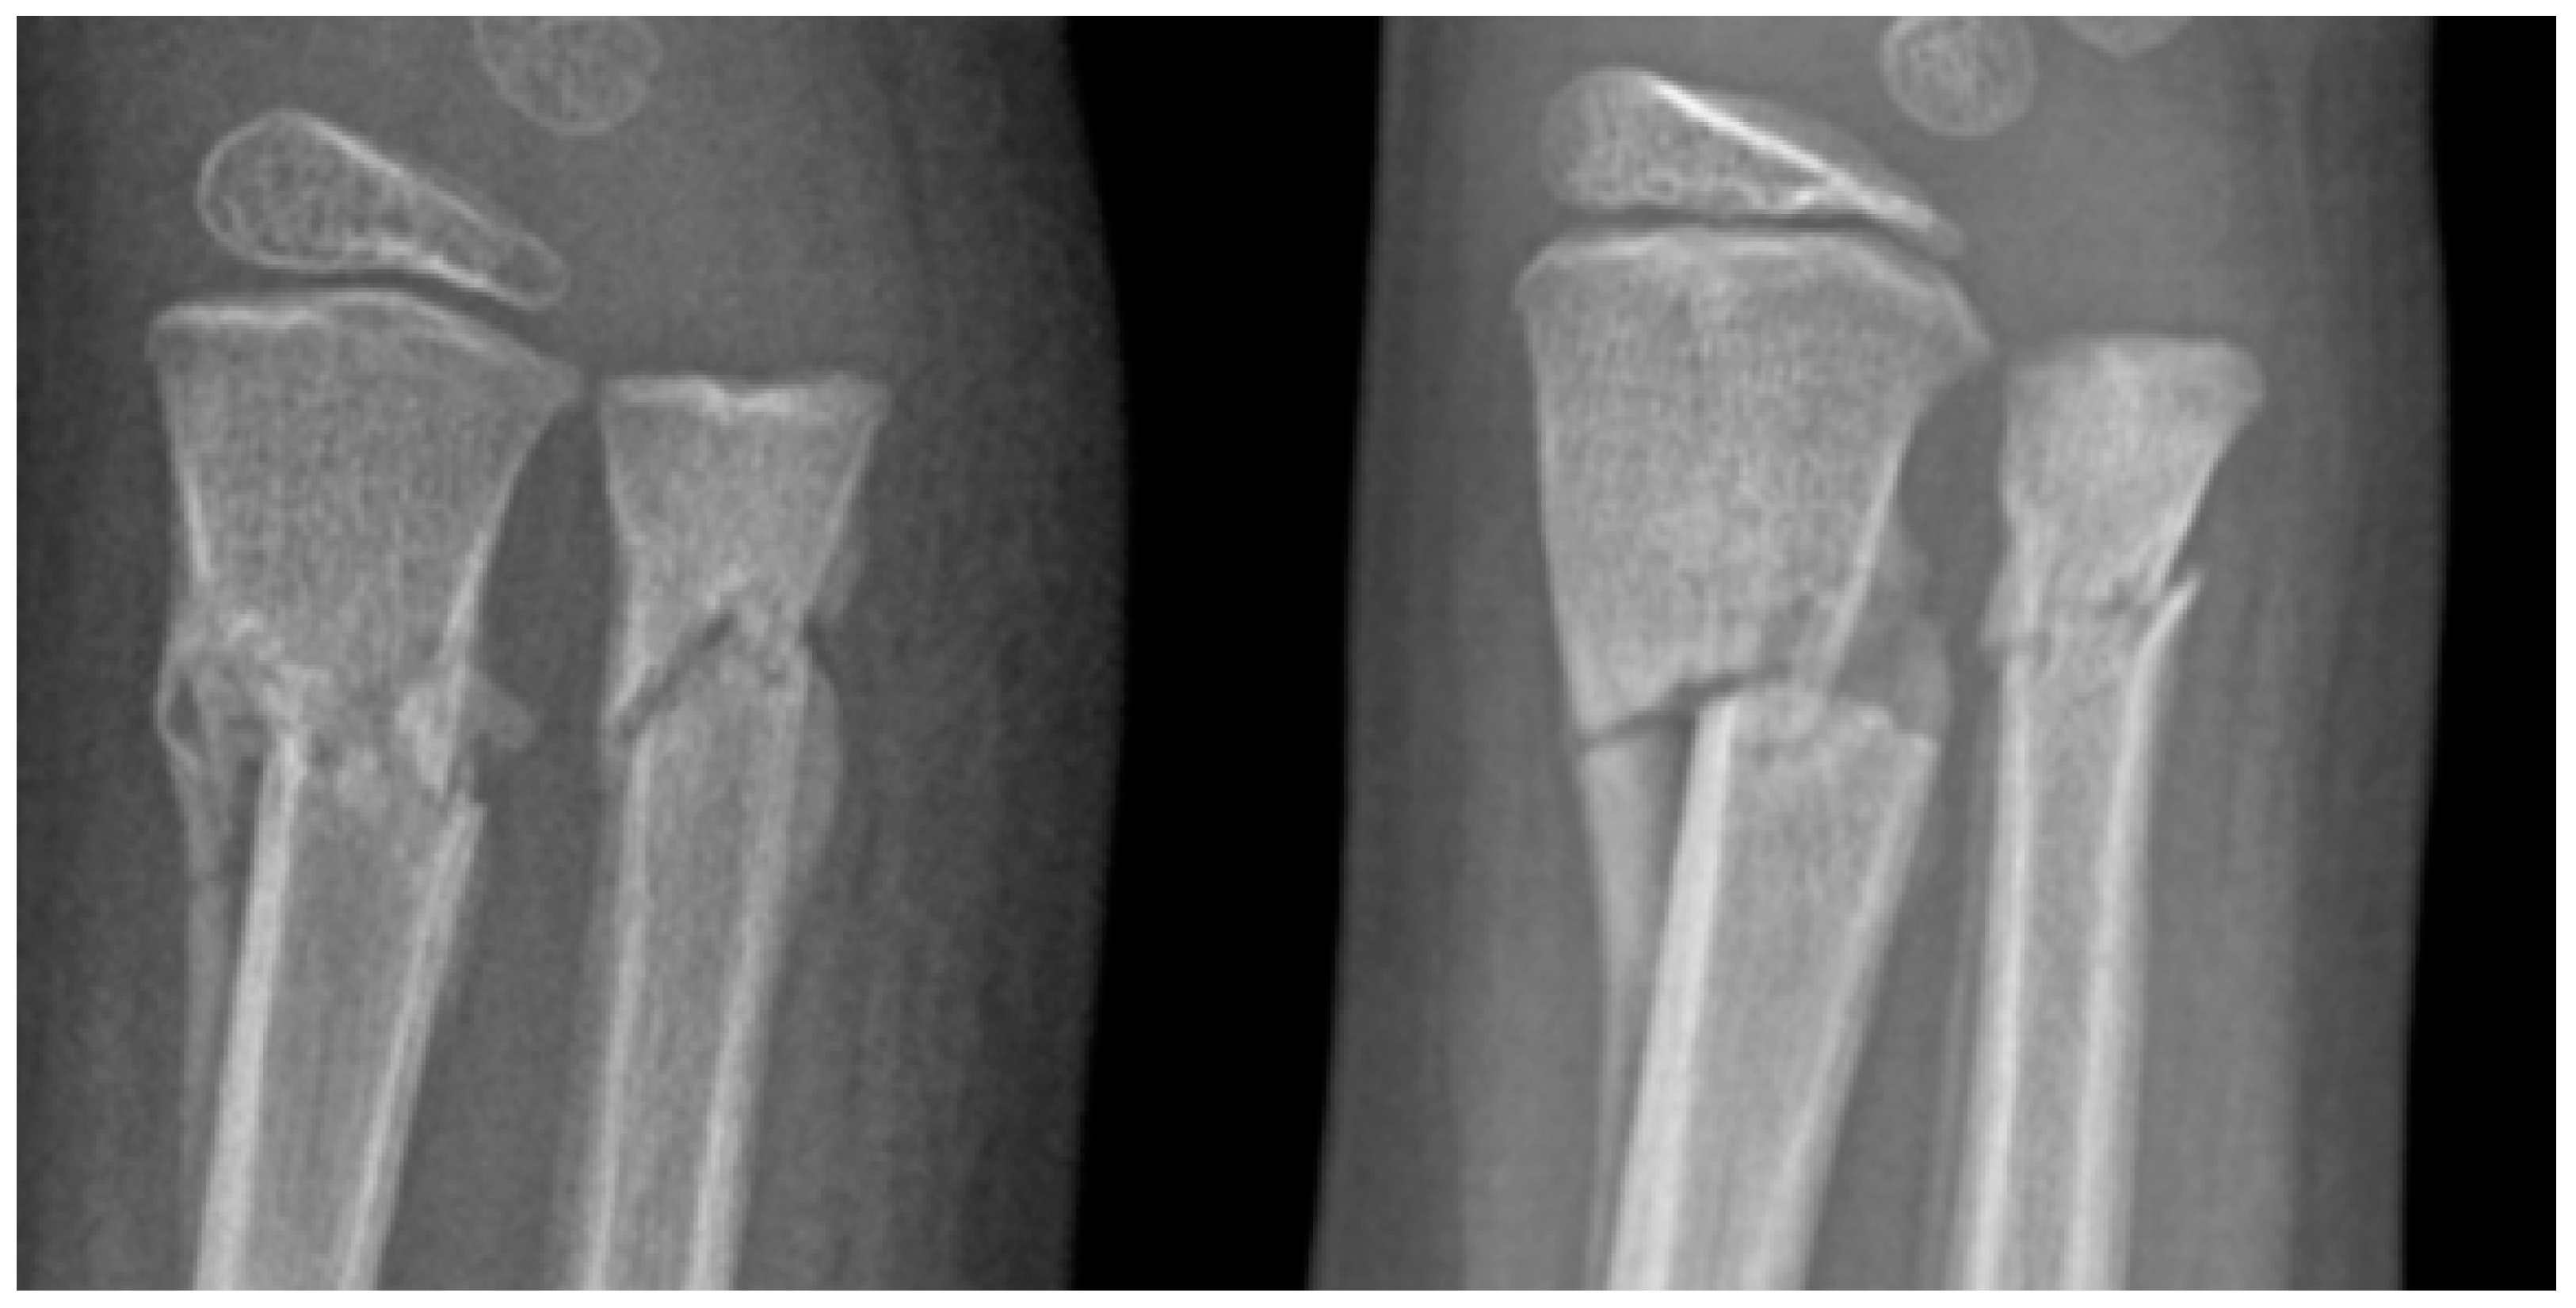

| Fracture Type | Total | Mean. Vit. D3 (ng/mL) | Mean Calcium (mg/dL) | Total | Mean. Vit. D3 (ng/mL) | Mean Calcium (mg/dL) |

| 1/3 distal of both forearm bones | 76 | 26.76 | 9.99 | 76 | 24.8 | 10.3 |

| 1/3 middle radius | 75 | 17.9 | 9.8 | 76 | 24.14 | 9.8 |

| Buckle fracture of the radius | 44 | 21.35 | 9.86 | 72 | 23.92 | 9.93 |

| 1/3 distal radius | 40 | 13.3 | 9.75 | 54 | 17.9 | 10.2 |

| 1/3 middle of both bones forearm | 40 | 24.23 | 9.87 | 45 | 24.5 | 9.67 |

| Buckle fracture of both bones of the forearm | 27 | 25.8 | 9.8 | 10 | 24.57 | 9.16 |